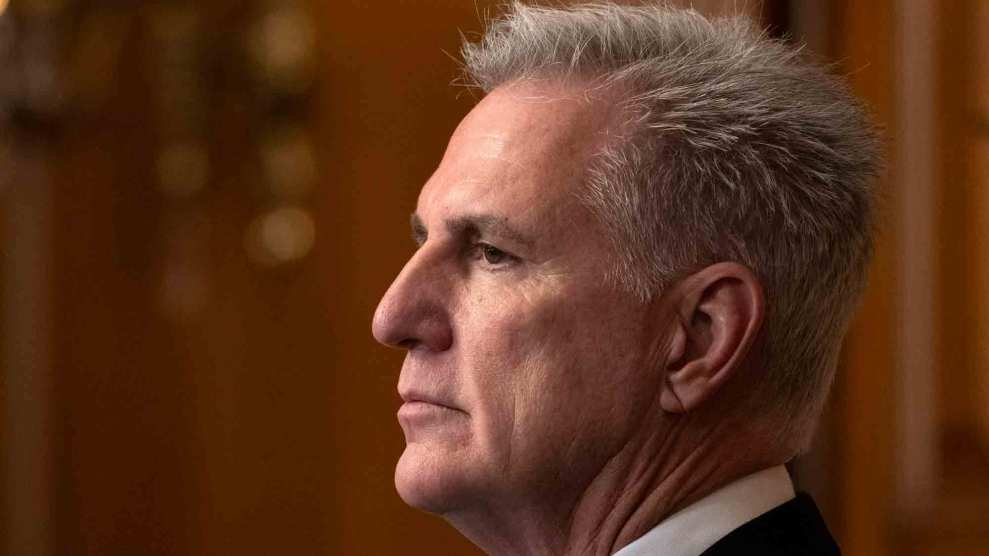

X-ray of a patient with advanced pulmonary tuberculosis.Credit: Centers for Disease Control via <a href="http://commons.wikimedia.org/wiki/File:Tuberculosis-x-ray-1.jpg">Wikimedia Commons</a>.